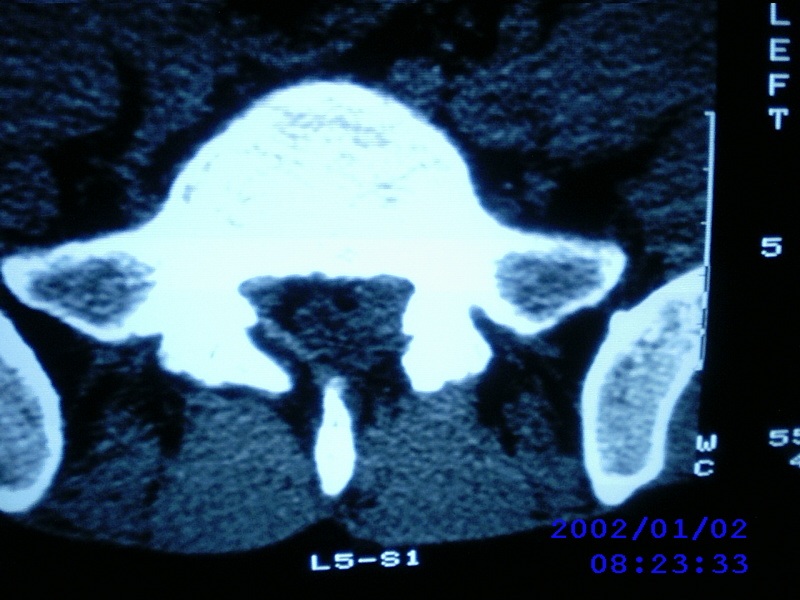

患者,男性,40岁,腰痛伴左下肢疼痛、麻木6年。5年前做过腰椎间盘手术,具体是哪个位置病人记不清了。

我拍的是l4-5、l5-s1

1)l4/5及l5/s1左侧椎板术后改变。2)l5/s1椎间盘突出,l5椎体下缘许莫氏结节。3)l4/5椎间盘膨出并突出。4)l3/4椎间盘膨出。

1)l4/5及l5/s1左侧椎板术后改变。2)l5/s1椎间盘突出,l5椎体下缘许莫氏结节。3)l4/5椎间盘膨出并突出。

1)l4/5及l5/s1左侧椎板术后改变。2)l5/s1椎间盘突出,l5椎体下缘许莫氏结节。3)l4/5椎间盘膨出并突出。4)l3/4椎间盘膨出。支持!